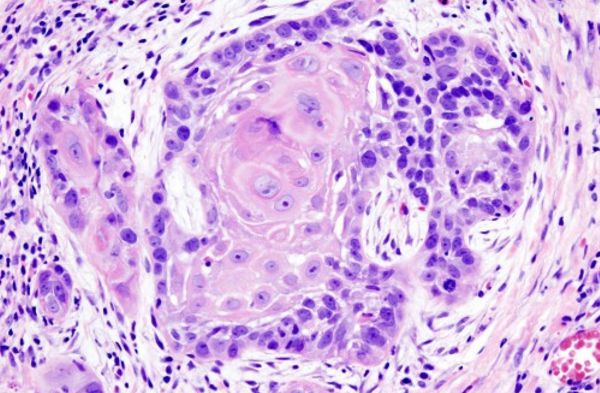

Histopathology

Histopathology (or histology) involves the examination of sampled whole tissues under the microscope. Histopathology tests are conducted by Doctorlab mainly to observe whether cancer cells are detected in a patient. Histopathologists are responsible for making tissue diagnoses and helping clinicians manage a patient's care.